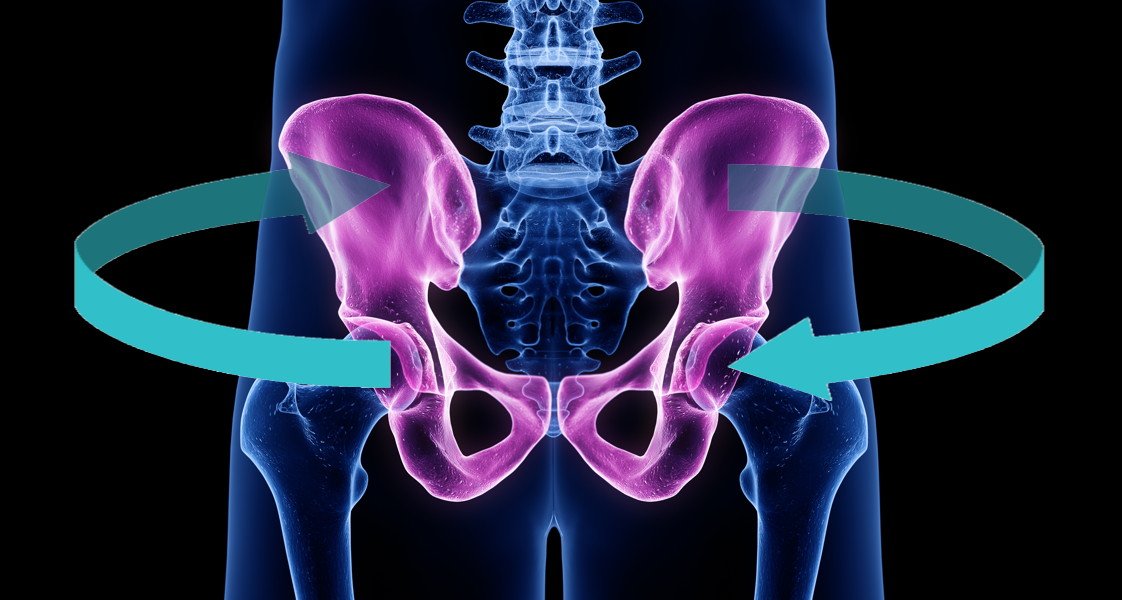

الميل الجانبي للحوض

يحدث عندما يكون أحد جانبي الحوض أعلى من الآخر.

قد يكون السبب عضليًا نتيجة شد عضلات أسفل الظهر من جانب واحد، أو هيكليًا مثل اختلاف طول الساقين أو بعض اضطرابات العمود الفقري.

هذا النوع من اعوجاج الحوض قد يسبب عدم توازن في المشي أو ميل الجسم إلى أحد الجانبين.

كيف يؤثر ميلان الحوض على العمود الفقري والمشي؟

الحوض يلعب دورًا محوريًا في استقرار الجسم أثناء الحركة.

عند حدوث اعوجاج الحوض يختل التوازن بين العمود الفقري والعضلات المحيطة به، وهو ما يؤثر على ما يعرف بالسلسلة الحركية للجسم.